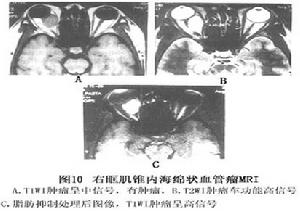

4.MRI 更明確顯示腫瘤的位置、範圍、邊界和周圍結構的關係。至關重要的是顯示腫瘤與視神經的關係,在這方面MRI優於CT利用SE脈衝序列在T1WI腫瘤為中等強度信號,信號強度低於脂肪,與眼外肌相似,比玻璃體高。在T2WI腫瘤為高信號,注射Gd-DTPA後可見信號明顯增高。觀察信號強度要考慮TR和TE長短,這兩個參數明顯影響信號強度。MRI顯示腫瘤內結構不及B型超音波。